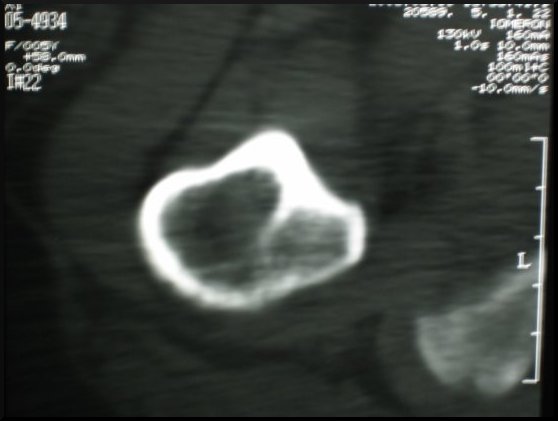

Dobierając skład chemiczny i strukturę materiału kompozytowego, z którego wykonujemy modele przeznaczone do szkoleń, główny nacisk położyliśmy na dokładne odtworzenie właściwości naturalnej kości. W tym celu poddaliśmy kość różnorodnym badaniom. Tą samą technikę zastosowaliśmy badając modele z materiałów kompozytowych.